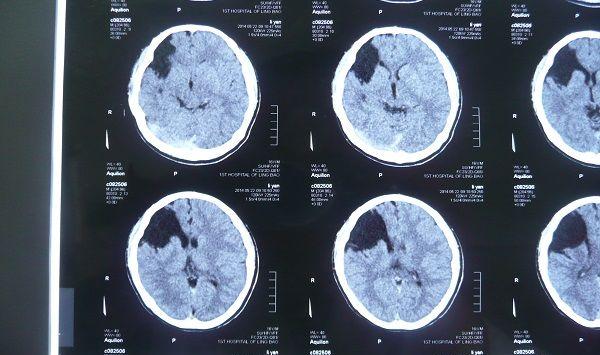

新生儿颅内出血并非疑难杂症,但由于患儿一般较小,且该病对患儿的影响极大,所以及时的护理和治疗十分关键,对于比较轻微的颅内出血是有可能自愈的,但严重时,颅内出血的并发症会直接影响孩子生命。当宝宝出现颅内出血的症状时,要早发现早治疗。

新生儿颅内出血的严重程度与出血部位和出血量有关,出血轻微的患儿可能没有任何症状,但严重者常常有以下表现,大人们一定要注意。

对于新生儿颅内出血要引起足够的重视,并积极的治疗,否则可能导致严重的后遗症,如智力低下、癫、脑性瘫痪脑回过小或小头畸形等。

凡是出现颅内出血症状的新生儿,应及时去医院检查诊断,确诊后积极治疗。